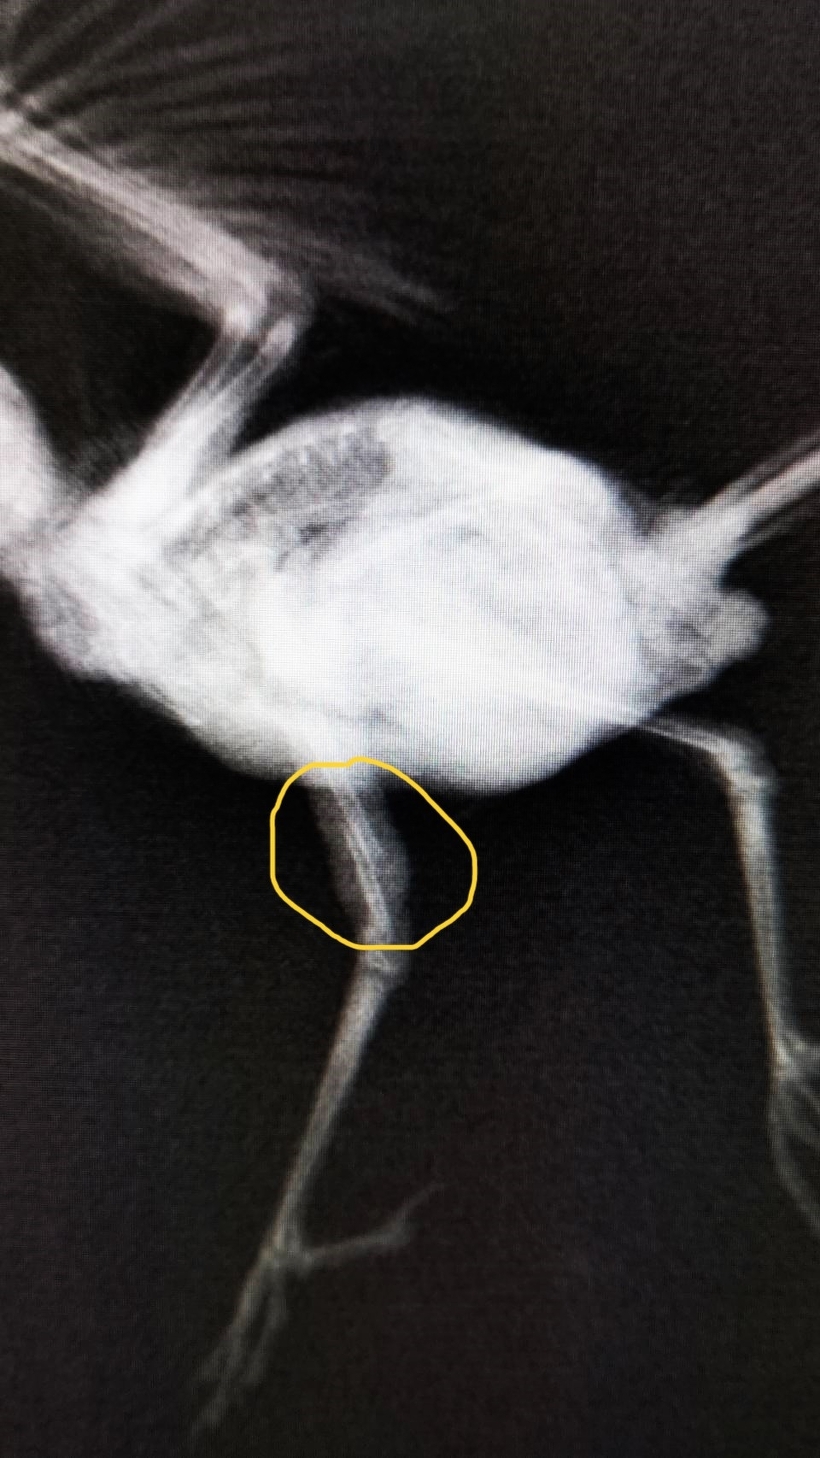

元気はありましたが右脚が変な方向を向いており、骨折していました。巣立ちの際に何らかの衝撃が加わってしまったのだと思われます。

脚がとても細いため直接骨髄内にピンを入れる方法ではなく、注射針にテープを巻いて副子を作成し骨折部位にあてて粘着包帯で巻いて外固定しました。

8月18日に脚の固定を外してみると、しっかり歩けて止まり木にもとまれており、骨も問題ない様子でした。